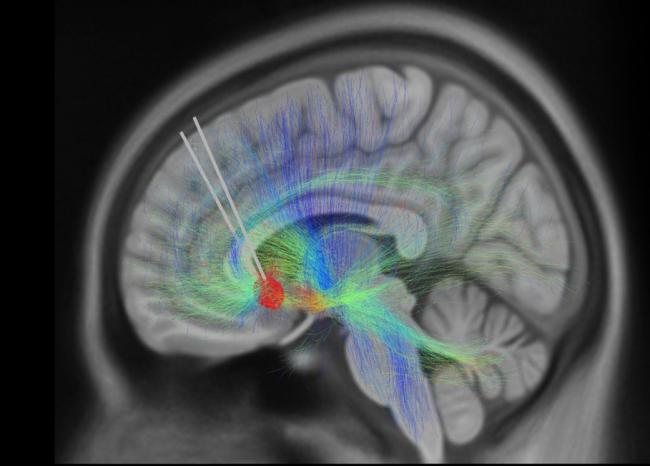

For most people with depression, taking antidepressant drugs provides relief. But some still struggle with depression even after trying two or more medications. For these patients, an experimental therapy called deep-brain stimulation (DBS) can sometimes help. The technique involves surgically implanting thin metal electrodes into specific brain regions. Electrical impulses are then delivered to modify brain activity.

A team of NIH-supported scientists aimed to find a more quantitative way to measure treatment success. Led by Drs. Christopher Rozell of Georgia Institute of Technology and Helen Mayberg of the Icahn School of Medicine at Mount Sinai, the team tested a new brain-stimulating device that can also record nearby electrical activity in patients’ brains. They hoped to identify electrical activity that might serve as a biomarker of recovery.

To gain insights into the brain area that was targeted by the DBS therapy, the team analyzed MRI data from brain scans collected before surgery. Damage to the white matter in these regions was linked to longer recovery times.